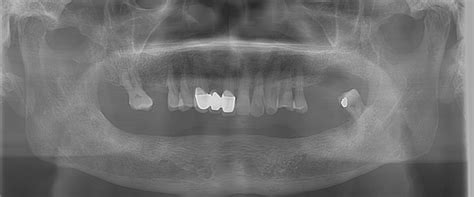

The versatility of Cone Beam CT has made it an indispensable tool in modern clinical environments. Its ability to provide cross-sectional data that 2D imaging simply cannot replicate allows for better diagnostic clarity. Below are some of the most common applications:

- Dental Implant Planning: Surgeons can precisely measure bone density and volume, ensuring implants are placed in the ideal position while avoiding vital anatomical structures like the mandibular nerve.

One of the most profound benefits is the diagnostic accuracy. Because the technology is not subject to the magnification or distortion inherent in 2D panoramic X-rays, measurements taken from a Cone Beam CT image are essentially 1:1 scale. This precision is vital for the success of complex surgeries, where millimeters can make the difference between a successful implant integration and nerve damage.